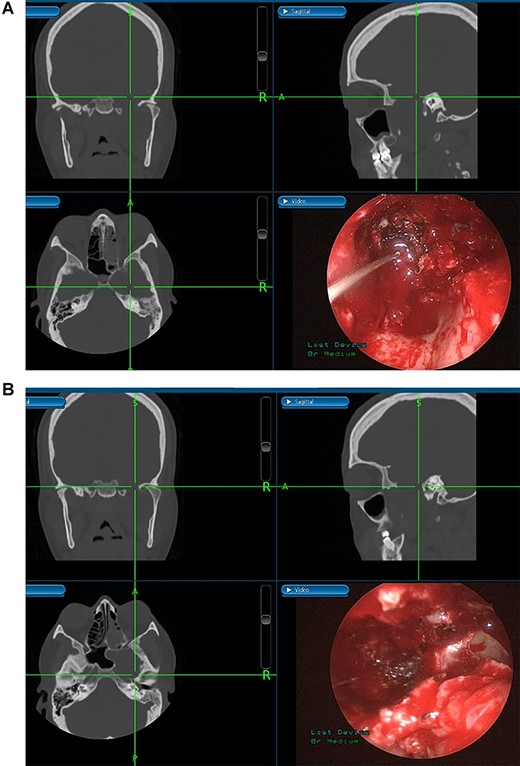

(A) Endoscopic view of the final surgical cavity after tumor removal. (B) Image-guided tumor removal from cavernous carotid artery.

The patient underwent an image-guided endonasal endoscopic tumor removal starting by endoscopic medial and posterior walls maxillectomies to control the tumor removal from the lateral sphenoid sinus and the infratemporal fossa after cauterization of the maxillary artery and sphenopalatine artery branches feeding the tumor. The tumor was dissected and removed from the cavernous (Fig. 3A) and petrous carotid artery in the middle cranial fossa (Fig. 3B). The middle cranial fossa’s dura was intact during the tumor removal (Fig. 3C). All the steps of tumor removal were controlled and monitored under image-guided navigation for accurate localization of tumor removal and avoidance of violation to the middle cranial fossa’s dura, or the brain, and the internal carotid artery in its cavernous and petrous segments (Fig. 4a and b).